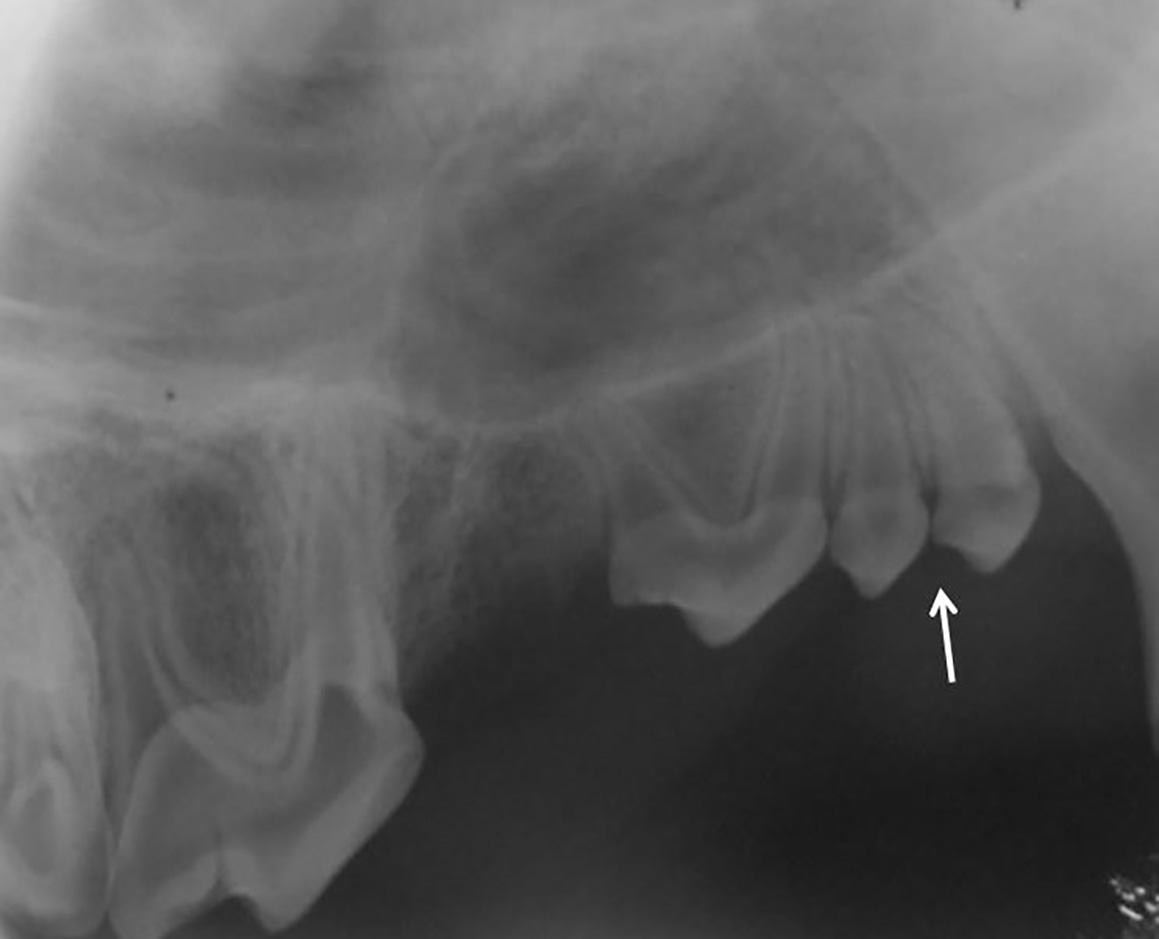

- En el gato, el foramen mentoniano se encuentra en el espacio interdental entre el diente canino y el tercer premolar mandibular o a nivel de este último (imagen 5).